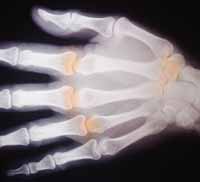

La osteoartritis o artrosis es un trastorno degenerativo

que afecta las articulaciones de la mano, columna vertebral, cadera y rodilla

caracterizado por degeneración del cartílago y formación de osteofitos. Clínicamente

¿Qué articulaciones afecta con más frecuencia la osteoartritis?

Manos.

¿Que son los osteofitos?

Los osteofitos son una de las principales características de la osteoartritis, son neoformaciones de cartílago osificado.